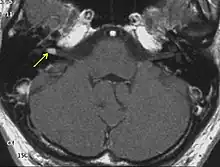

Schwannoma of the N. Vestibularis

The so-called acoustic neuroma of NF2 is in fact a schwannoma of the nervus vestibularis, or vestibular schwannoma. The misnomer of acoustic neuroma is still often used. The vestibular schwannomas grow slowly at the inner entrance of the internal auditory meatus (meatus acousticus internus). They derive from the nerve sheaths of the upper part of the nervus vestibularis in the region between the central and peripheral myelin (Obersteiner-Redlich-Zone) within the area of the porus acousticus, 1 cm from the brainstem.